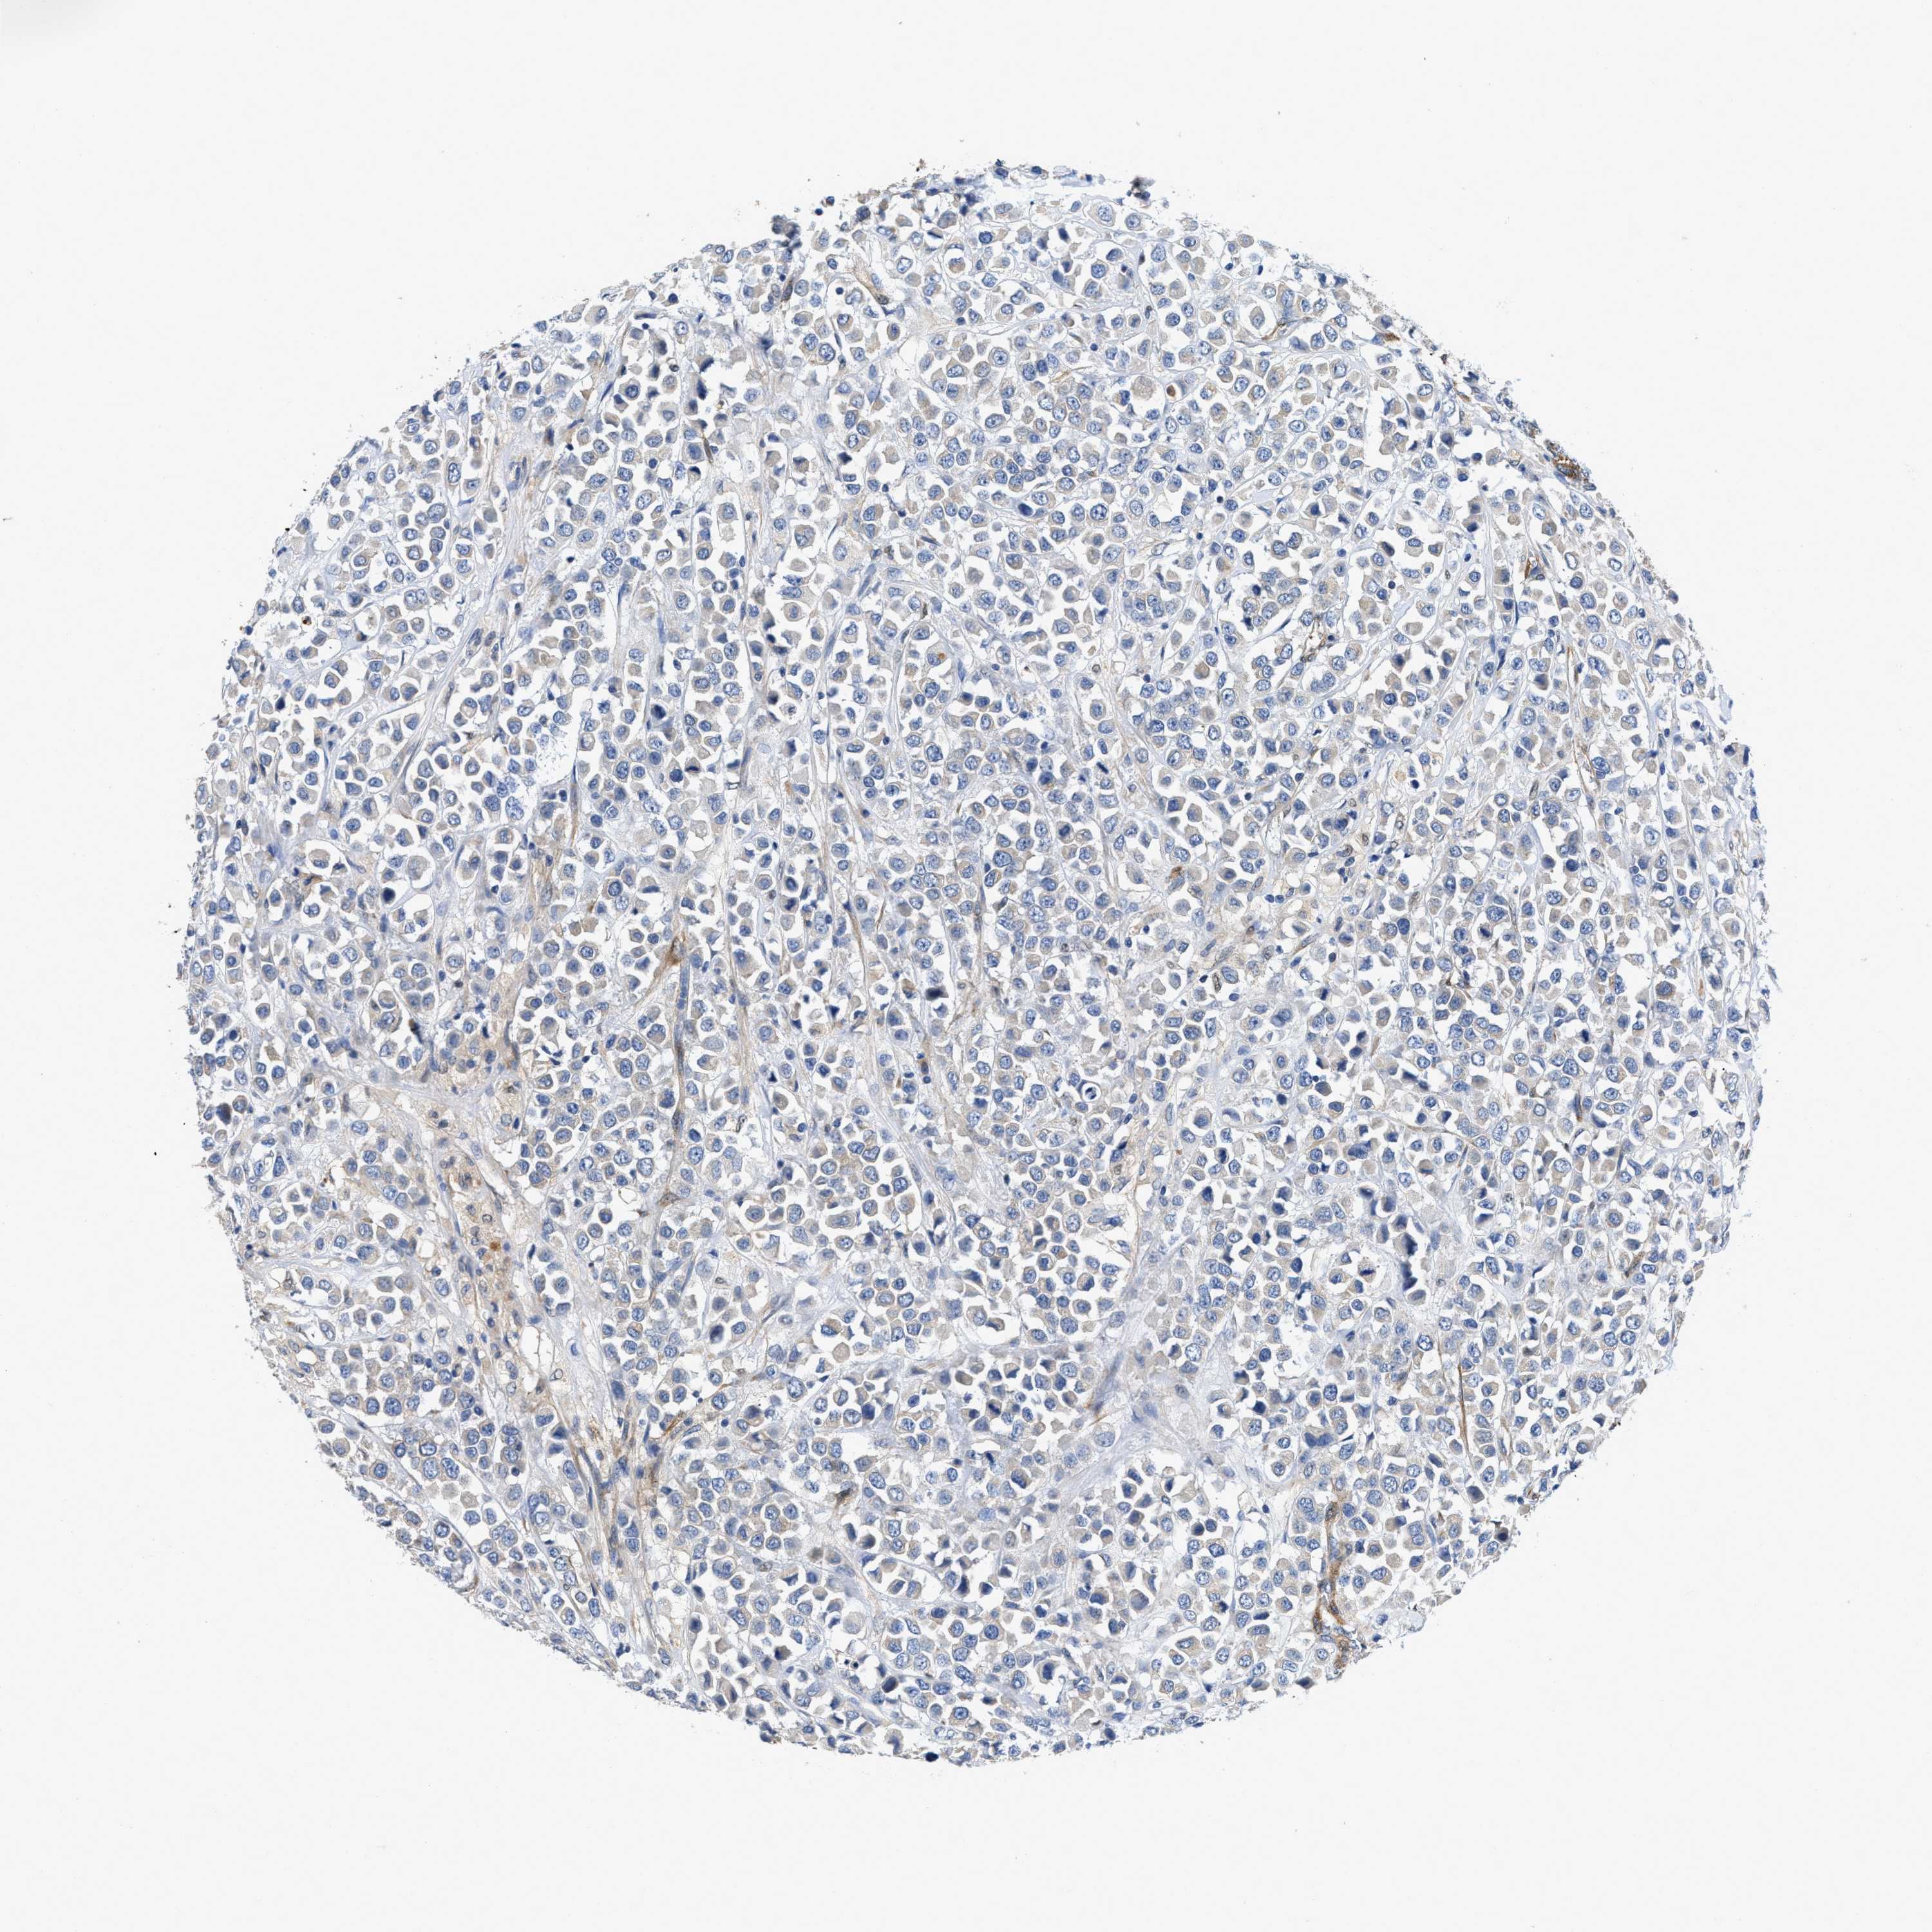

CANCER BREAST CANCER Show tissue menu

BRCA TCGA BRCA VALIDATION PROTEIN EXPRESSION